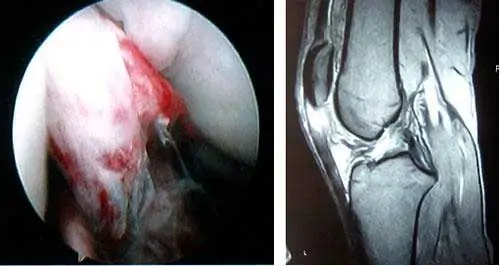

La prueba más sensible y específica es la resonancia magnética. Mediante esta prueba, no sólo se verifica la rotura del ligamento cruzado anterior, sino que además, se pueden valorar las posibles lesiones asociadas como las meniscales, las del cartílago o las de otros ligamentos.

Ligamento cruzado anterior de la rodilla roto. En la imagen de RMN se observa la ausencia del LCA,

queda una imagen blanca, de vacío, donde debería estar el ligamento.